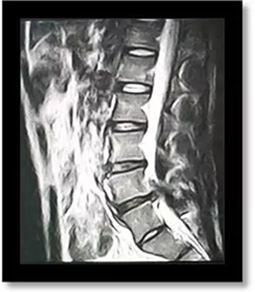

(術(shù)前)

劉志安副院長經(jīng)查看MRI(核磁共振成像)結(jié)果后,顯示小姚腰5/骶1椎間盤突出,髓核左下方游離,情況已經(jīng)比較嚴重,遂收住入院。